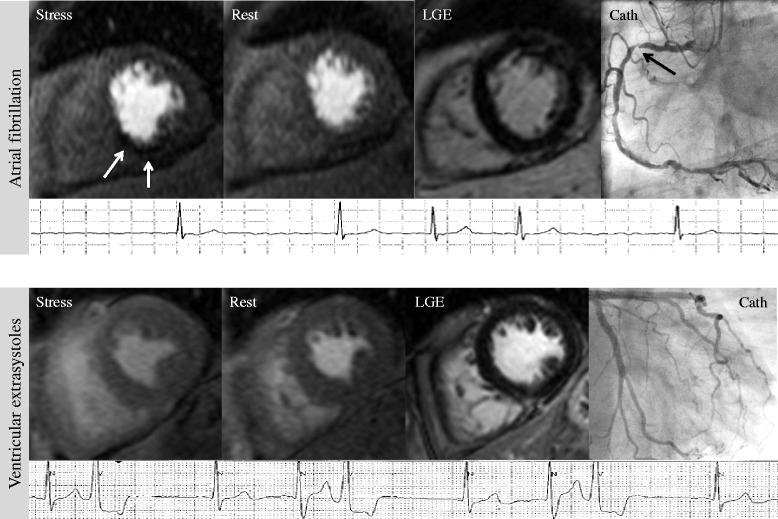

One hundred fifty-nine patients were included (n = 64 atrial fibrillation, n = 87 frequent ventricular extrasystoles, n = 8 frequent supraventricular extrasystoles). Of these, n = 72 had suspected CAD, and n = 87 had known CAD. Diagnostic accuracy of the adenosine stress CMR for detection of significant CAD was 73 % for the entire population (sensitivity 72 %, specificity 76 %). Diagnostic accuracy was 75 % (sensitivity 80 %, specificity 74 %) in patients with suspected CAD, and 74 % (sensitivity 71 %, specificity 79 %) in the group with known CAD. For different types of arrhythmia, diagnostic accuracy of CMR was 70 % in the atrial fibrillation group, and 79 % in patients with ventricular extrasystoles. On a per coronary territory analysis, diagnostic accuracy of CMR was 77 % for stenosis of the left and 82 % for stenosis of the right coronary artery.

The present data demonstrates good diagnostic performance of adenosine stress CMR for detection of significant coronary stenosis in patients with arrhythmia presenting for work-up of suspected CAD, or work-up of ischemia in known CAD. This holds true for a per patient, as well as for a per coronary territory analysis.